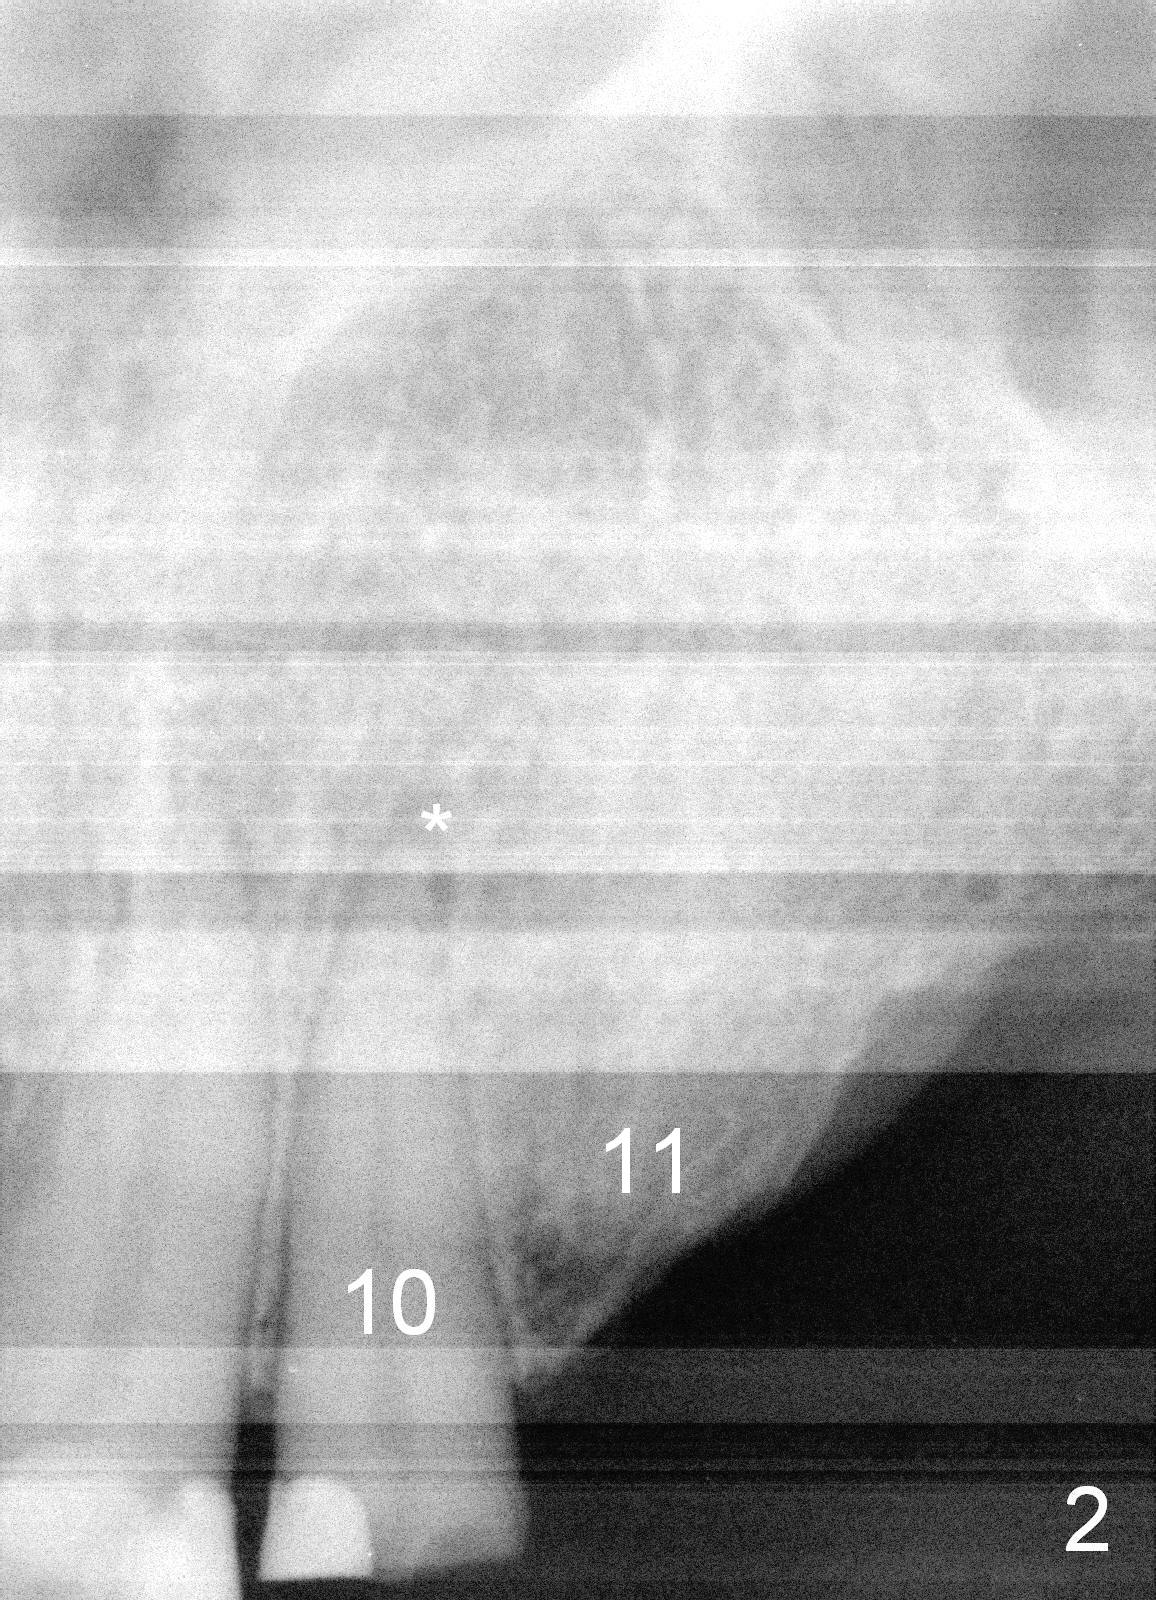

A 70-year-old man (TF) requests implant restoration for the upper left quadrant first (Fig.1), exactly #10 and 11 first (Fig.2-4). There is periapical radiolucency associated with the residual root at #10 (Fig.2 *). Local antibiotic will be Metronidazole. The root of #10 is long and large. The bone at #11 looks loose. Long implants will be placed (Fig.4). Osteotomy preparation should be less.

When initial osteotomy is established at #10 with insertion of a parallel pin, use 4.5 mm implant spacer to determine the initial point for #11 implant site (Fig.4: 6.49 (red line)-2=4.49 mm). 70岁男多个牙齿缺失,5.5年前就诊,同意在10-13位点植牙(图一)。